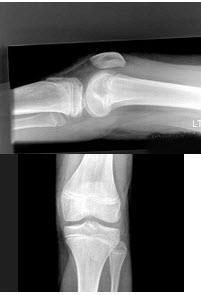

23、单项选择题

男,62岁,左膝疼痛、活动不便,结合图像,最可能的诊断是()

A.髌骨软化症

B.粉碎性骨折

C.膝关节结核

D.退行性骨关节病

E.风湿性关节炎